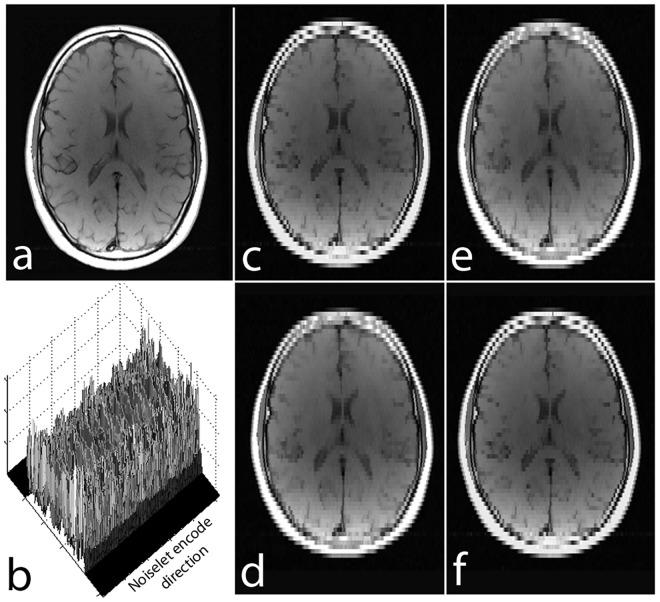

The incoherence between measurement and sparsifying transform matrices and the restricted isometry property (RIP) of measurement matrix are two of the key factors in determining the performance of compressive sensing (CS). In CS-MRI, the randomly under-sampled Fourier matrix is used as the measurement matrix and the wavelet transform is usually used as sparsifying transform matrix. However, the incoherence between the randomly under-sampled Fourier matrix and the wavelet matrix is not optimal, which can deteriorate the performance of CS-MRI. Using the mathematical result that noiselets are maximally incoherent with wavelets, this paper introduces the noiselet unitary bases as the measurement matrix to improve the incoherence and RIP in CS-MRI. Based on an empirical RIP analysis that compares the multichannel noiselet and multichannel Fourier measurement matrices in CS-MRI, we propose a multichannel compressive sensing (MCS) framework to take the advantage of multichannel data acquisition used in MRI scanners. Simulations are presented in the MCS framework to compare the performance of noiselet encoding reconstructions and Fourier encoding reconstructions at different acceleration factors. The comparisons indicate that multichannel noiselet measurement matrix has better RIP than that of its Fourier counterpart, and that noiselet encoded MCS-MRI outperforms Fourier encoded MCS-MRI in preserving image resolution and can achieve higher acceleration factors. To demonstrate the feasibility of the proposed noiselet encoding scheme, a pulse sequences with tailored spatially selective RF excitation pulses was designed and implemented on a 3T scanner to acquire the data in the noiselet domain from a phantom and a human brain. The results indicate that noislet encoding preserves image resolution better than Fouirer encoding.

测量矩阵与稀疏变换矩阵之间的非相干性以及测量矩阵的受限等距特性(RIP)是决定压缩感知(CS)性能的两个关键因素。在CS-MRI中,随机欠采样的傅里叶矩阵被用作测量矩阵,小波变换通常被用作稀疏变换矩阵。然而,随机欠采样的傅里叶矩阵与小波矩阵之间的非相干性并非最优,这会降低CS-MRI的性能。利用噪声小波与小波具有最大非相干性这一数学结果,本文引入噪声小波酉基作为测量矩阵,以改善CS-MRI中的非相干性和RIP。基于一项经验性RIP分析,该分析比较了CS-MRI中的多通道噪声小波和多通道傅里叶测量矩阵,我们提出了一种多通道压缩感知(MCS)框架,以利用MRI扫描仪中使用的多通道数据采集的优势。在MCS框架中进行了模拟,以比较不同加速因子下噪声小波编码重建和傅里叶编码重建的性能。比较结果表明,多通道噪声小波测量矩阵的RIP比其傅里叶对应矩阵更好,并且噪声小波编码的MCS-MRI在保留图像分辨率方面优于傅里叶编码的MCS-MRI,并且可以实现更高的加速因子。为了证明所提出的噪声小波编码方案的可行性,设计并在3T扫描仪上实现了一种具有定制空间选择性射频激发脉冲的脉冲序列,以从体模和人脑获取噪声小波域中的数据。结果表明,噪声小波编码比傅里叶编码更好地保留了图像分辨率。